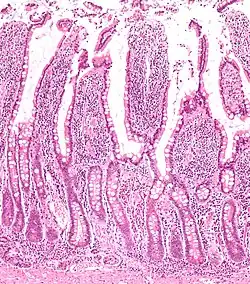

Lieberkühn-Krypten

Lieberkühn-Krypten (lat.: Glandulae intestinales), auch bekannt als Darmdrüsen, Lieberkühn-Drüsen sowie Cryptae intestinales, sind etwa 0,2 bis 0,4 mm tiefe schlauchförmige, teilweise verzweigte Einsenkungen des Epithels im Bereich der Schleimhaut des Dünn- und Dickdarms. Benannt wurden sie nach dem Berliner Arzt und Anatomen Johann Nathanael Lieberkühn (1711–1756).

Die Lieberkühnschen Krypten dienen der Oberflächenvergrößerung und Sekretion sowie nach neueren Erkenntnissen der Steuerung des Eisenhaushaltes im menschlichen Körper durch regulatorische Proteine. Entdeckt wurden sie 1688 von Marcello Malpighi, jedoch beschrieb sie Lieberkühn als Erster 1745 in seiner „Dissertatio de fabrica et actione villorum intestinorum tenuium hominis“.